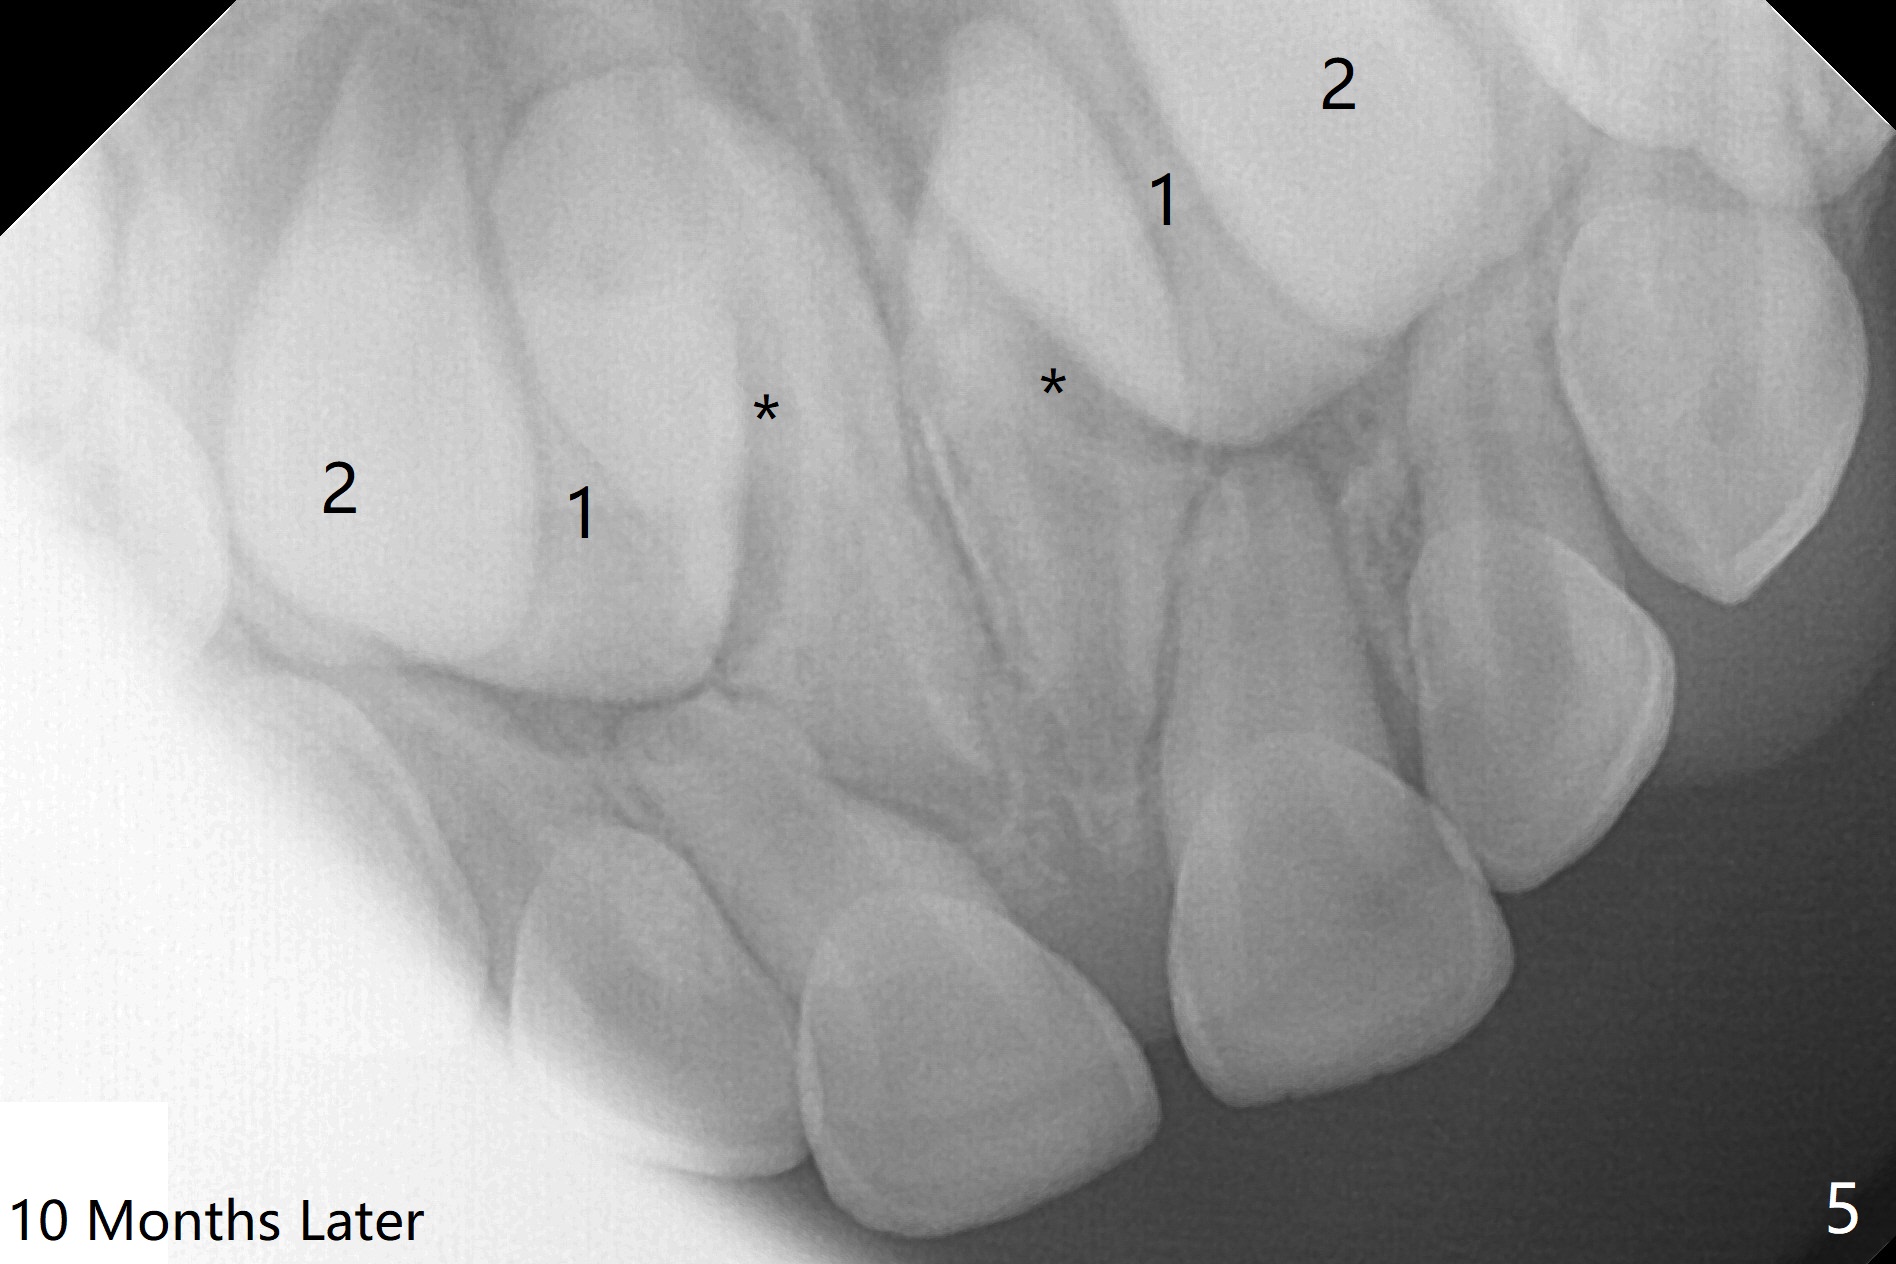

PA is taken 10 months later (Fig.5).  The roots of the supernumerary teeth (*) elongate, while the permanent centrals (1) have descended as the same level as the laterals (2).  The divergent centrals seem not be able to cause root resorption of the deciduous ones.  The parents have hesitated to accept surgical removal.  This PA (Fig.6) is taken 6 months later (as compared to Fig.5).  The apices of the supernumerary teeth (*) appear to have closed, while the permanent centrals (1) remain as the same level as the laterals (2).  The divergent centrals seem not be able to cause root resorption of the deciduous ones.  The patient is superactive.